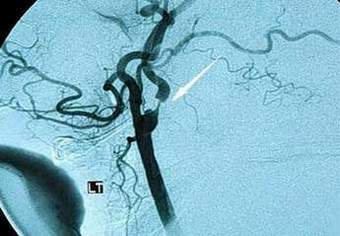

喷鼻式疫苗能预防中风(图)

据英国广播公司报道,喷鼻式疫苗很快将帮助高危人群避免患中风,这种疫苗由美国中风和神经性疾病研究所研制,其作用建立在使用E-选择蛋白基础上,新疫苗已顺利通过动物实验。在研究过程中给一组专门培育的血压过高的实验鼠注射疫苗,这些实验鼠的特点是产生中风的危险非常高,结果这实验鼠患局部缺血中风的风险比注射安慰剂的对照组降低16倍。

科学家同时指出,注射疫苗的实验鼠一般不会患出血性中风或脑溢血。研究人员认为,原因在于淋巴细胞在E-选择蛋白作用下会产生阻止炎症并减少血管受损的因子,同时疫苗不会影响血压。尽管疫苗效果令人难忘,但是英国中风协会代表在接受英国广播公司记者采访时指出,已有相当有效的检查血压各种方法,这些方法能明显降低中风的危险,转向健康饮食、适当运动、戒烟和戒酒都可以达到明显效果。